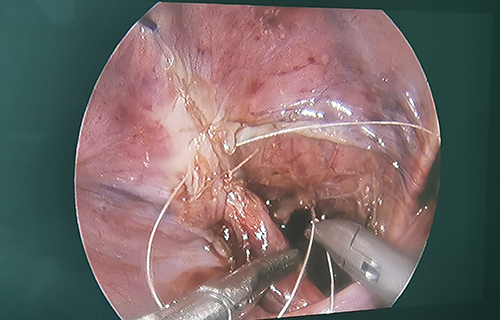

3个小时手术,完成再植

术前准备完毕。10月15日,栾志勇主任、谢方达副主任为佳佳行输尿管远端狭窄微创手术,在其肚脐周围打了3个直径5mm的小孔,在腹腔镜下顺利实施了输尿管膀胱再植。手术用时仅为3小时,出血量也比较少。

“如果开刀手术,需要在腹部做横切口,对孩子的损伤是比较大的。在保证手术效果的基础上,微创手术对孩子的损伤小,美观程度良好,术后恢复比较快。”栾志勇主任说。

腹腔镜下输尿管膀胱再植手术的成功,标志着a片网站 针对泌尿外科疾病的治疗完全实现微创个体化,涵盖肾脏及肾上腺实体肿瘤、囊性病变、肾盂积水、重复肾脏、输尿管膀胱反流、输尿管梗阻等上、下尿路重建的重症及常见病的治疗,也标志着a片网站 泌尿外科治疗达到东北地区领先水平。